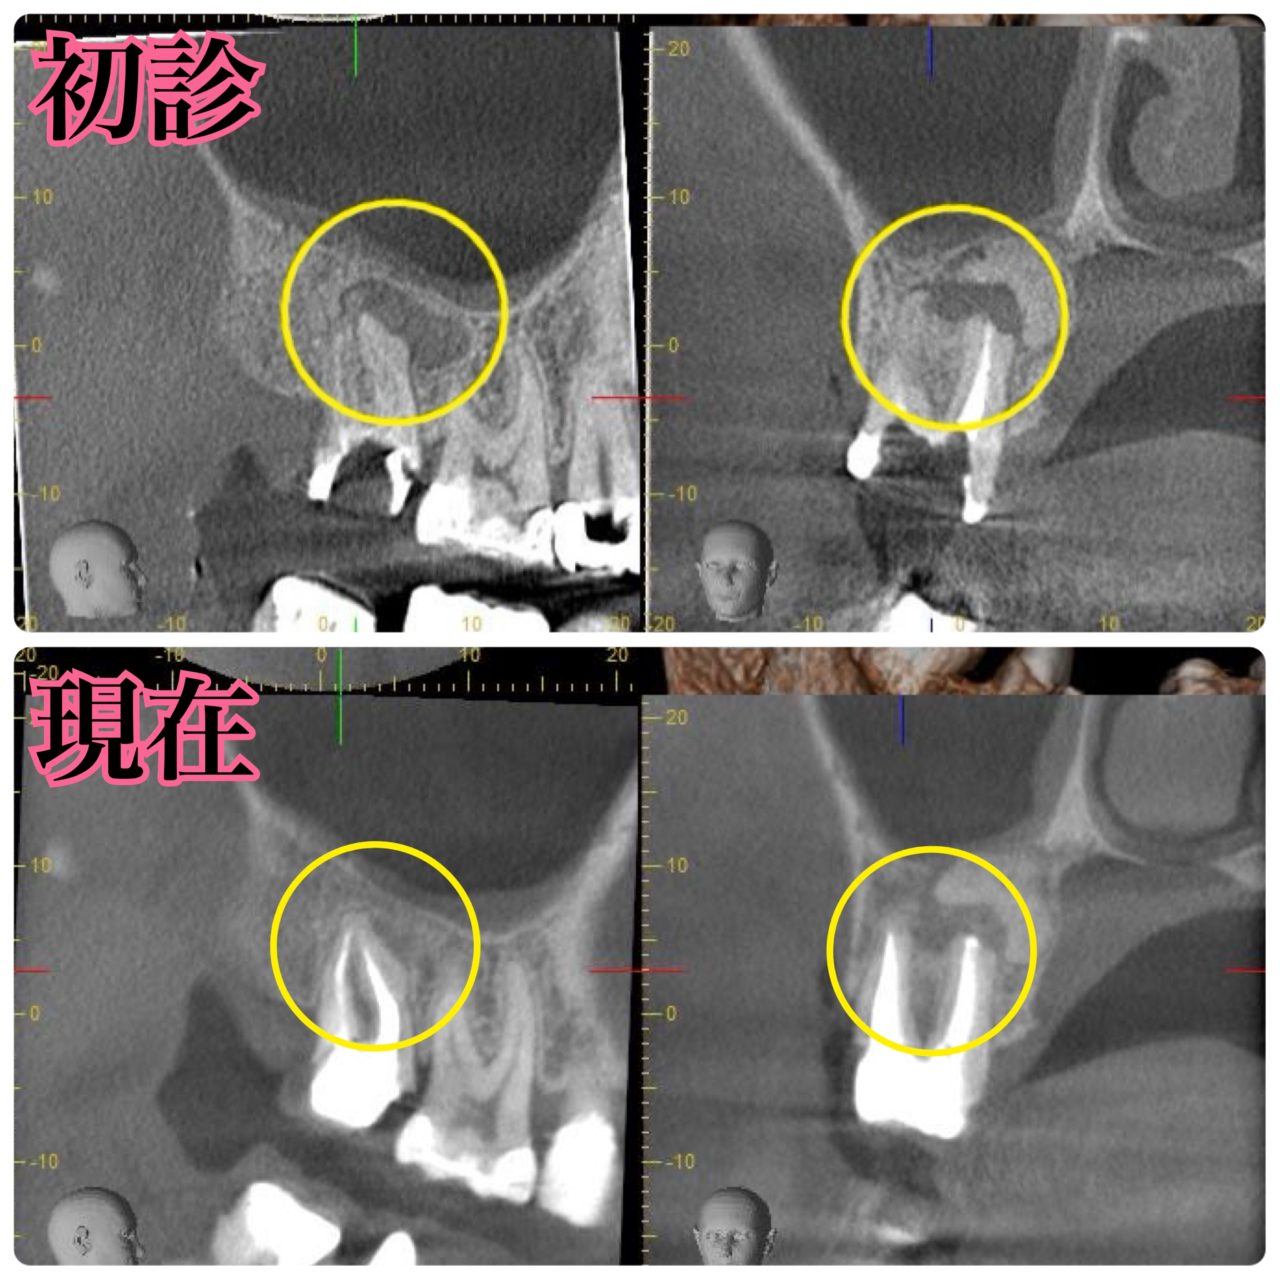

診断:CTによる精密検査で見つかった複雑な感染源

CTでしっかりと診断を行ったところ、とても深刻な状況でした。根管治療が重要ですが、それだけでは完全な治癒が望めない場合もあり、歯槽骨の再生を促す外科的処置が必要になることもあります。

根尖病変によりCT上で黒く写っていた部分が白っぽくなっているのがわかりますか?

溶けていた部分の歯槽骨が回復しているということです!

また、上顎洞の肥厚は収まり、頬側の歯槽骨もくっきり映っています。予想以上に歯槽骨が回復しているので、今後外科的処置をしなくても良いのではないかと判断しました。大きなダメージがあった歯なので補綴物を入れた後も欠かさずに経過観察を行い、少しでも長くご自身の歯で生活して頂きたいと思います。